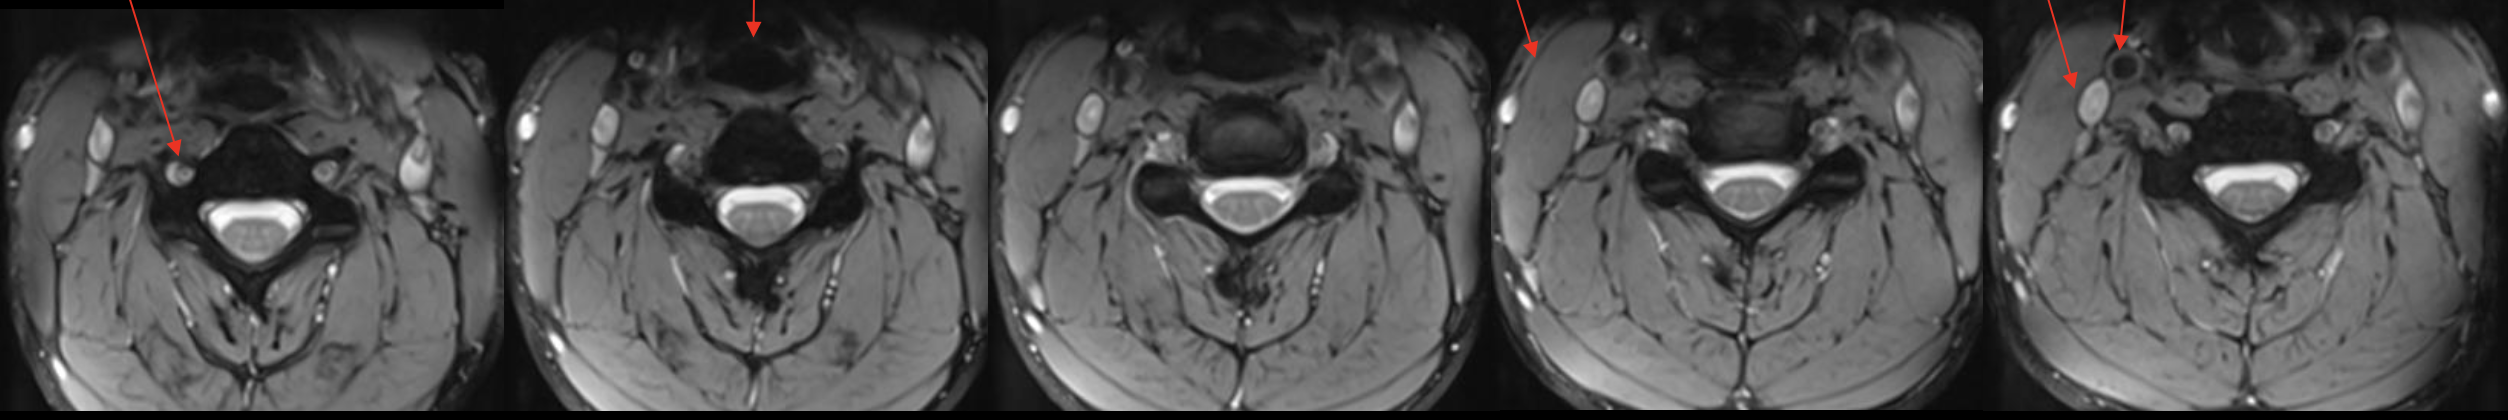

椎动脉

Vertebral artery

气管

Trachea

胸锁乳突肌

Sternocleidomastoid